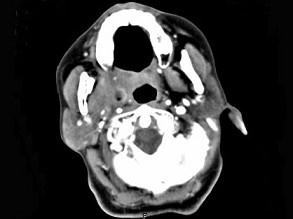

问题 女,52岁,咽喉部疼痛半个月,伴低热,CT如图所示,可能诊断为 ( )

选项 A、咽旁淋巴瘤 B、咽旁转移癌 C、咽部神经鞘瘤 D、鼻咽血管纤维瘤 E、咽旁脓肿

答案 E